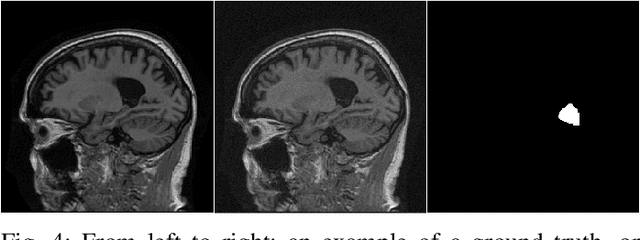

Abstract:Virtual staining, or in-silico-labeling, has been proposed to computationally generate synthetic fluorescence images from label-free images by use of deep learning-based image-to-image translation networks. In most reported studies, virtually stained images have been assessed only using traditional image quality measures such as structural similarity or signal-to-noise ratio. However, in biomedical imaging, images are typically acquired to facilitate an image-based inference, which we refer to as a downstream biological or clinical task. This study systematically investigates the utility of virtual staining for facilitating clinically relevant downstream tasks (like segmentation or classification) with consideration of the capacity of the deep neural networks employed to perform the tasks. Comprehensive empirical evaluations were conducted using biological datasets, assessing task performance by use of label-free, virtually stained, and ground truth fluorescence images. The results demonstrated that the utility of virtual staining is largely dependent on the ability of the segmentation or classification task network to extract meaningful task-relevant information, which is related to the concept of network capacity. Examples are provided in which virtual staining does not improve, or even degrades, segmentation or classification performance when the capacity of the associated task network is sufficiently large. The results demonstrate that task network capacity should be considered when deciding whether to perform virtual staining.